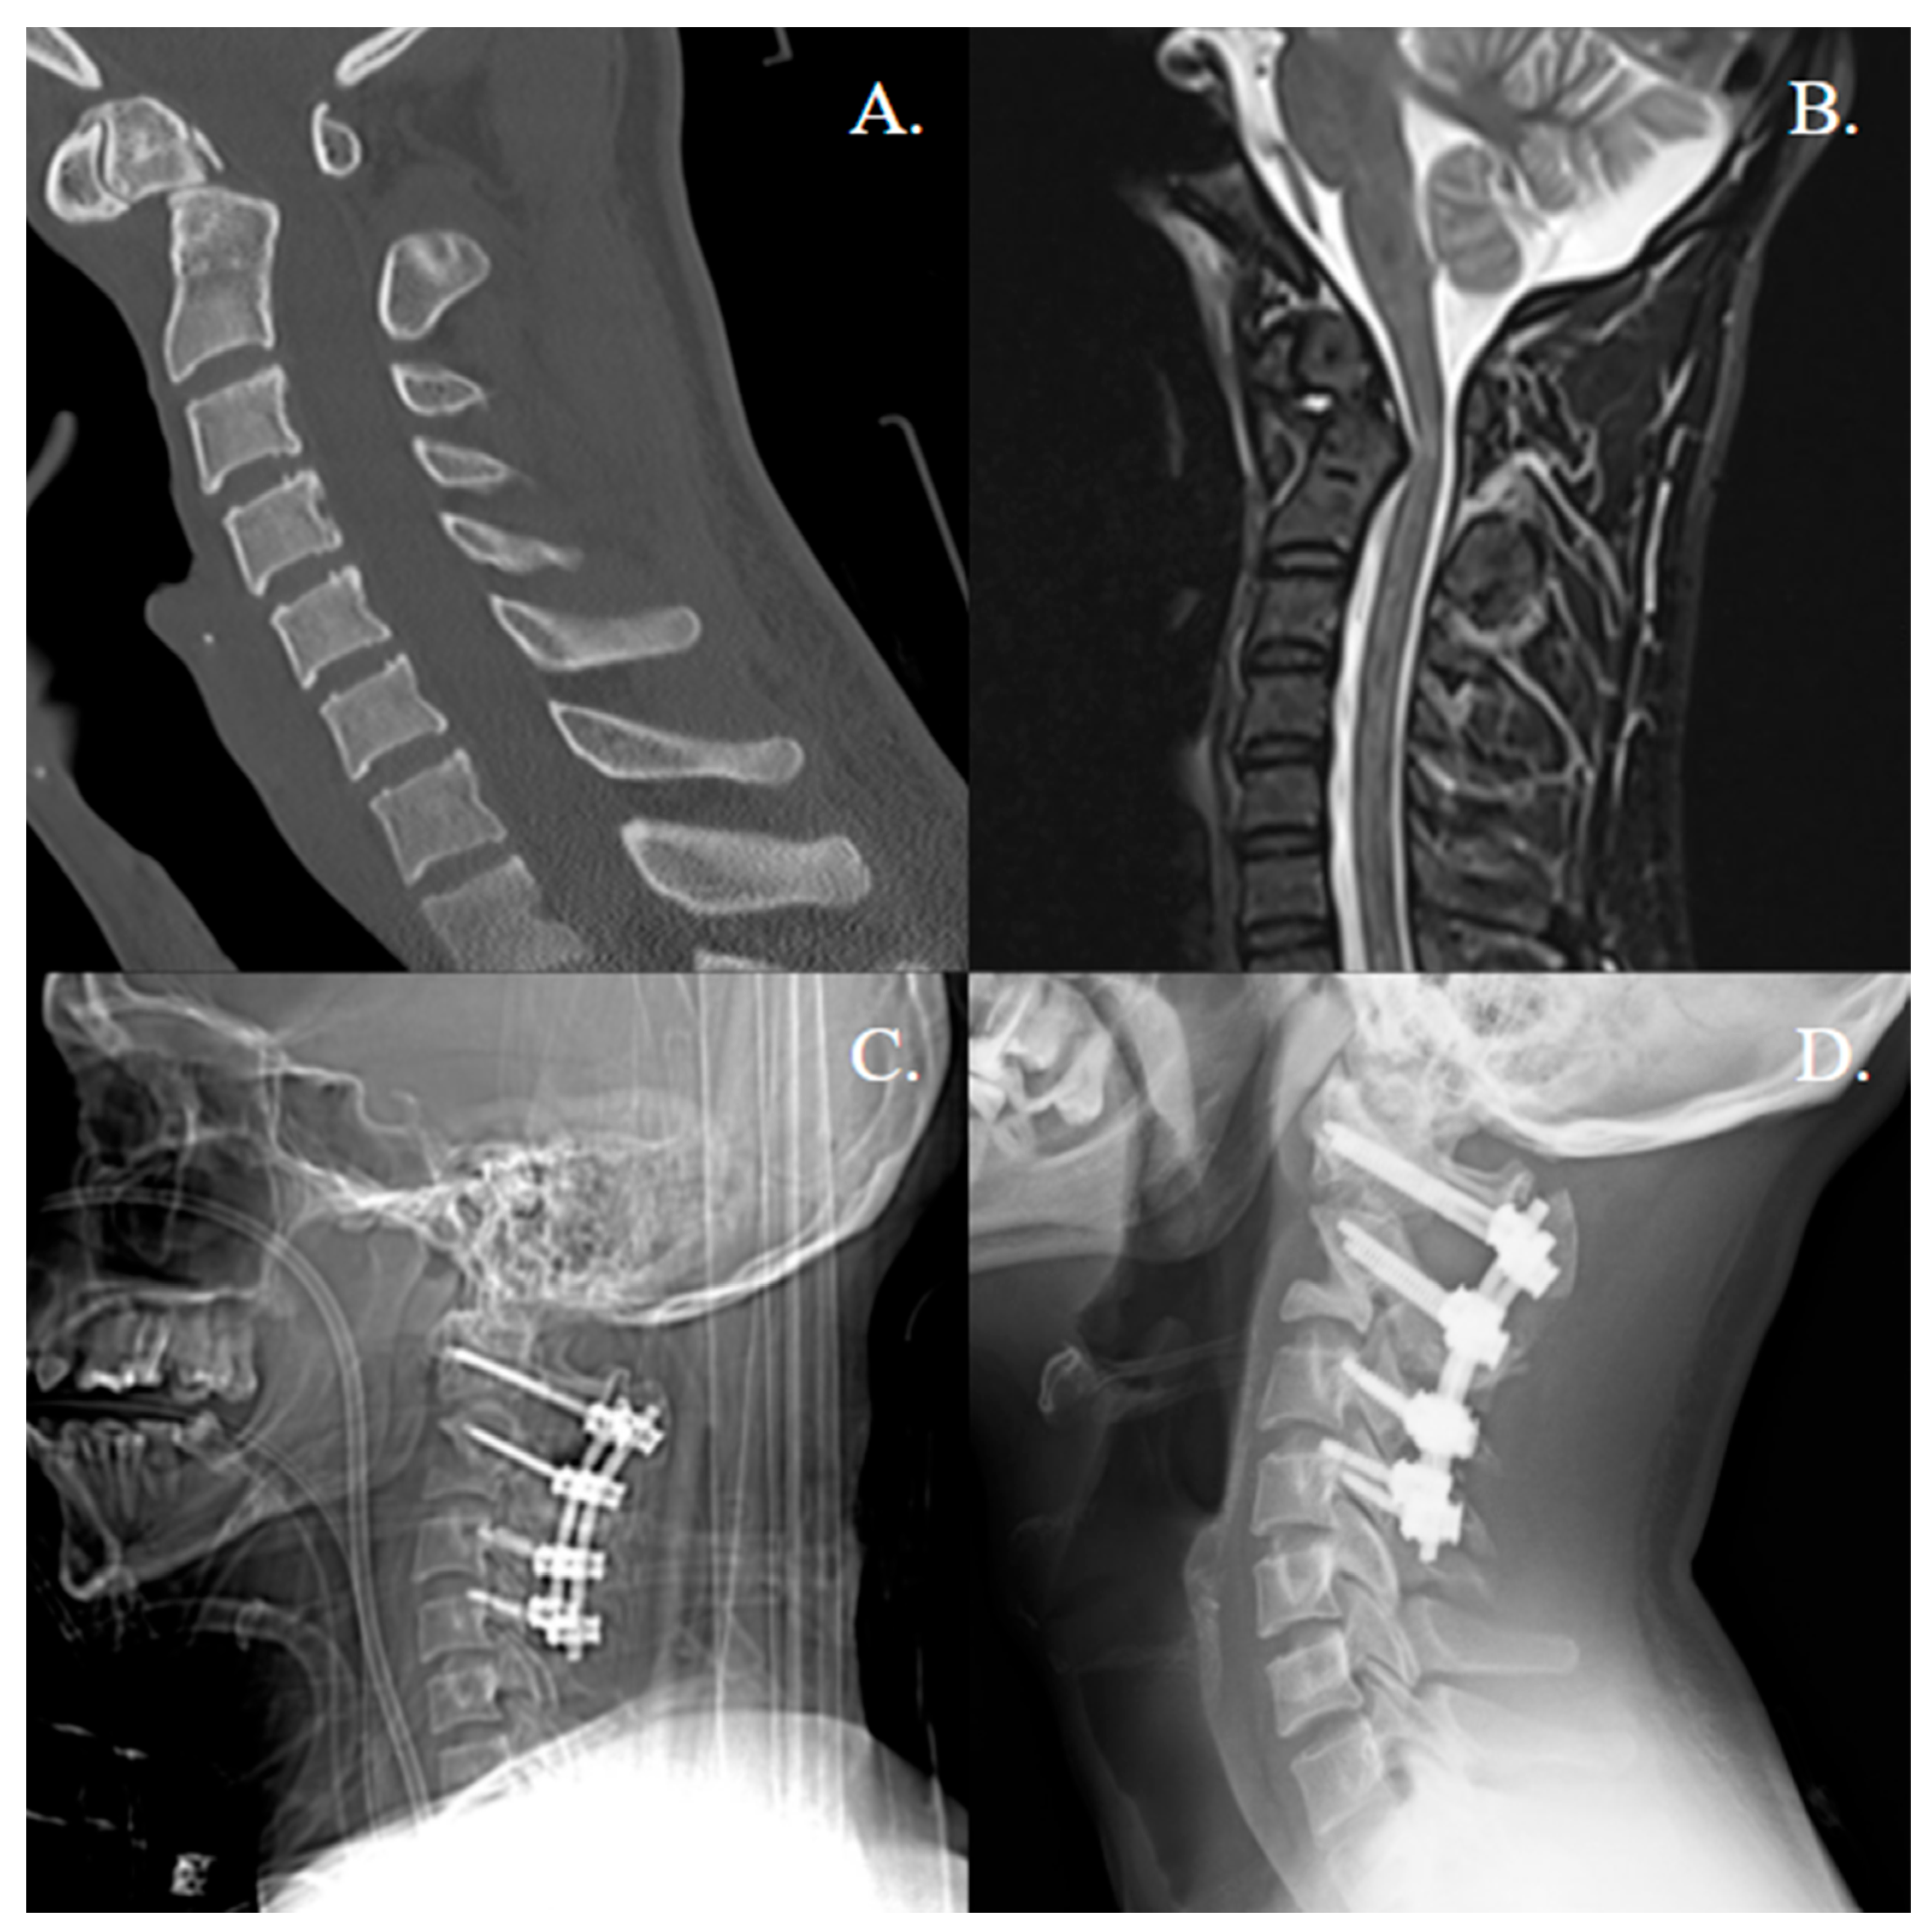

| 1 | 45, M | Degenerative | C1 lateral mass screws bilaterally, C2 translaminar screws bilaterally, titanium rod | N | DBX, rhBMP-2 (XX small kit, 0.82 mg/mL) | 26 |

| 2 | 29, F | Trauma | C1 lateral mass screws bilaterally, C2 translaminar screws bilaterally. Sublaminar Songer cables at C1 and posterior to C2 spinous process, titanium rod | N | DBX, femoral head structural allograft, rhBMP-2 (XX small kit, 0.82 mg/mL) | 25 |

| 3 | 51, M | Trauma | C1 lateral mass screws bilaterally, 1 C2 pars and 1 C2 pedicle screw, titanium rods | N | rhBMP-2 (X small kit, 1.62 mg/mL) | 3 |

| 4 | 28, F | Trauma | C1 lateral mass screws bilaterally, C2 pedicle screws bilaterally, titanium rod | N | DBX, local autograft, rh-BMP-2 (half of a XX small kit, 0.41 mg/mL) | 20 |

| 5 | 80, F | Trauma | C1 lateral mass screws bilaterally, C2 pedicle screws bilaterally, titanium rod, cross connector at C1 | N | DBX, local autograft, rhBMP-2 (X small kit, 1.62 mg/mL) | 4 |

| 6 | 33, F | Trauma | C1 lateral mass screws bilaterally, C2 pedicle screws bilaterally, titanium rod | N | DBX, local autograft, rhBMP-2 (half of a XX small, 0.41 mg/mL) | 69 |

| 7 | 77, M | Trauma | C1 lateral mass screws bilaterally, C2 pedicle screws bilaterally | Y | DBX, local autograft, rh-BMP-2 (XX small kit, 0.82 mg/mL) | 10 |

| 8 | 80, M | Trauma | C1 lateral mass screws bilaterally, C2 pedicle screws bilaterally, titanium rods | Y | DBX, local autograft, rh-BMP-2 (XX small kit, 0.82 mg/mL) | 3 |

| ID | Surgical Complications | Revision (Y/N) | Fusion on Latest Follow-Up Imaging (Y/N) | Atlantoaxial Instability Clinically or in Dynamic Imaging? (Y/N) | Imaging Follow Up (Time, Type) |

|---|---|---|---|---|---|

| 1 | C1 screw breakage | N, avoided re-op due to complete bony fusion | Y | N | 25 months, X-ray |

| 2 | None | N | Y | N | 25 months, X-ray |

| 3 | None | N | Early signs of fusion | N | 3 months, CT |

| 4 | None | N | Y | N | 19 months, CT |

| 5 | None | N | N | N | 4 months, CT |

| 6 | None | N | Y | N | 15 months, X-ray |

| 7 | None | N | Early signs of fusion | N | 3 months, CT |

| 8 | None | N | Early signs of fusion | N | 3 months, X-ray |